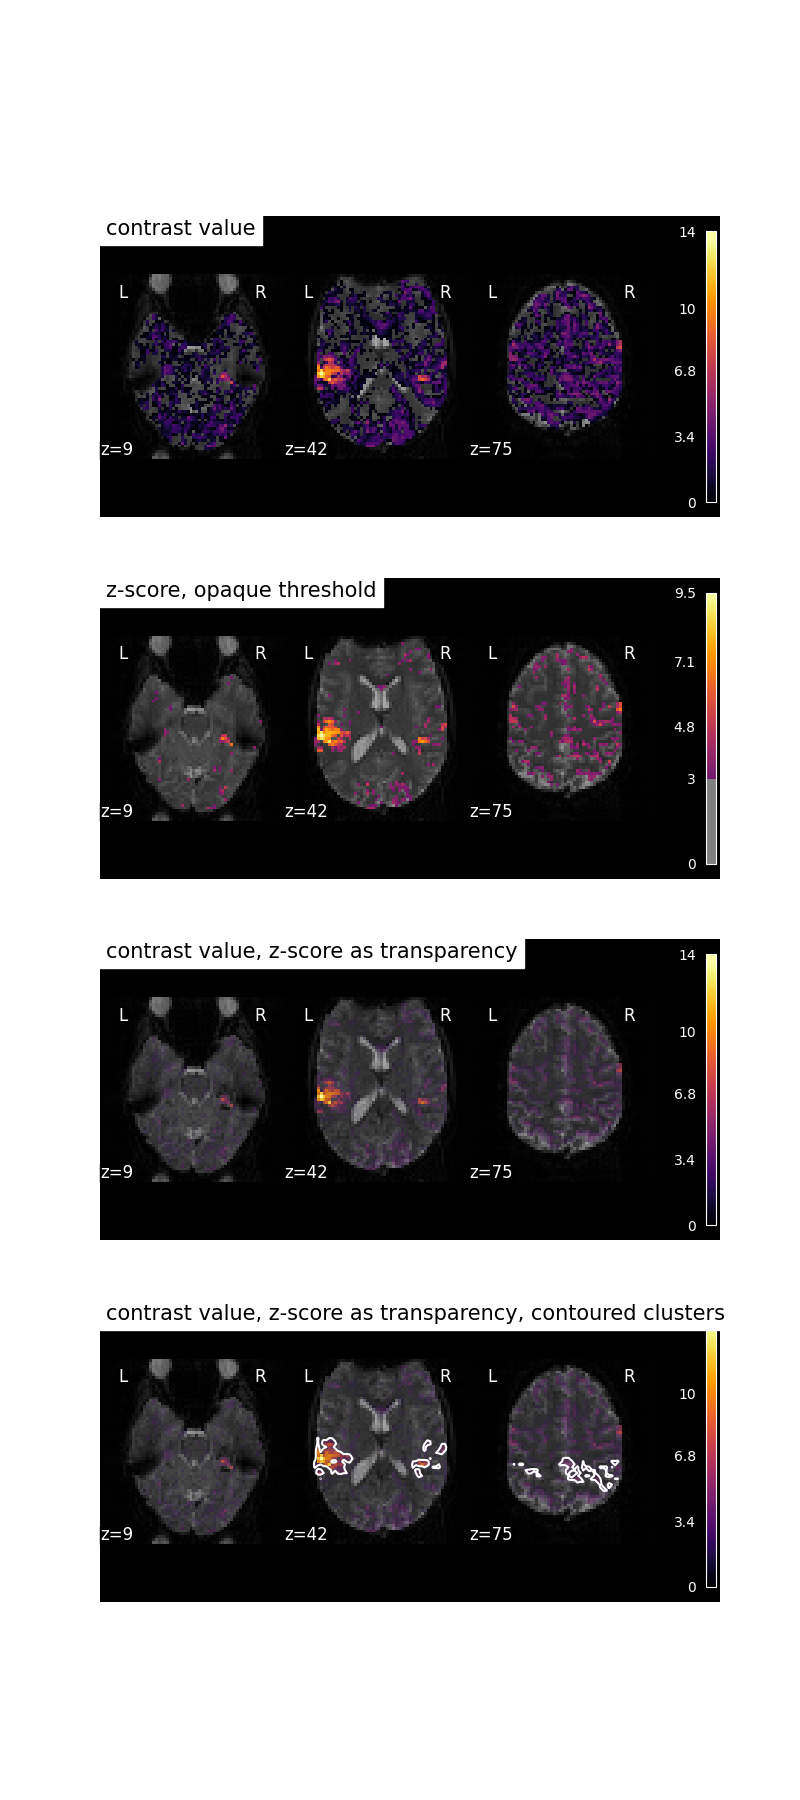

Transparent thresholding on GLM results¶

You can also use different images as ‘transparency’ layer.

For example, on the output of a GLM, you can visualize the contrast values and use their z-score as transparency.

We will show this on a simple block paradigm GLM.

Here we will:

have a look at the statistical value for our contrast,

have a look at their Z score with opaque contrast,

use the Z score as transparency value,

finally we will threshold the Z-score to identify the significant clusters (fdr=0.05, 500 voxels) and plot those as contours.

plot_stat_map(

results["stat"],

title="contrast value",

axes=axes[0],

**plotting_config,

)

results["z_score"],

title="z-score, opaque threshold",

threshold=3,

axes=axes[1],

title="contrast value, z-score as transparency",

axes=axes[2],

transparency=results["z_score"],

display = plot_stat_map(

title="contrast value, z-score as transparency, contoured clusters",

axes=axes[3],

clean_map, threshold = threshold_stats_img(

alpha=0.05,

height_control="fdr",

cluster_threshold=500,

two_sided=False,

display.add_contours(clean_map, filled=False, levels=[threshold], colors=["w"])